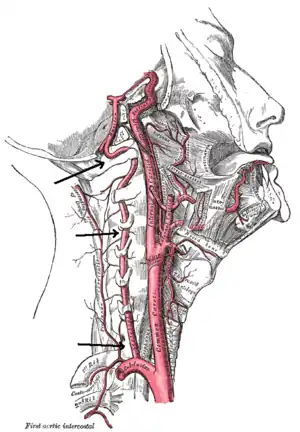

Arteries of the neck, with arrows indicating the right vertebral artery

The vertebral arteries arise from the subclavian artery, and run through the transverse foramen of the upper six vertebrae of the neck. After exiting at the level of the first cervical vertebra, its course changes from vertical to horizontal, and then enters the skull through the foramen magnum. Inside the skull, the arteries merge to form the basilar artery, which joins the circle of Willis. In total, three quarters of the artery are outside the skull; it has a high mobility in this area due to rotational movement in the neck and is therefore vulnerable to trauma. Most dissections happen at the level of the first and second vertebrae. The vertebral artery supplies a number of vital structures in the posterior cranial fossa, such as the brainstem, the cerebellum and the occipital lobes. The brainstem harbors a number of vital functions (such as respiration) and controls the nerves of the face and neck. The cerebellum is part of the diffuse system that coordinates movement. Finally, the occipital lobes participate in the sense of vision.[2]